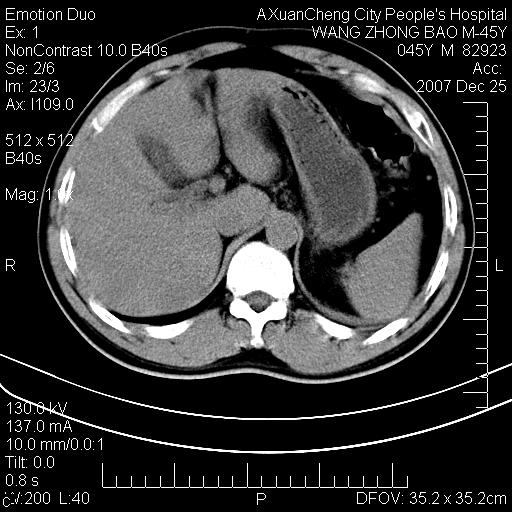

以下是引用qiuleiyu在2007-12-25 18:14:00的发言:[br]胰腺增大,周边渗出改变,肾前筋膜明显增厚,示少量积液.胆囊壁毛糙,周边少许渗出,胆总管壁厚,异常强化,然扩张不明显.结合病程急短;考虑;胆管炎,胆囊炎,胆源性胰腺炎可能大,请结合实验室检查及随访.

以下是引用lisihao在2007-12-25 14:23:00的发言:[br]急性水肿型胰腺炎[br]依据:1、胰腺弥漫性肿大,边缘稍毛糙;[br] 2、双侧肾周筋膜增厚,尤以左侧为甚(重要征象)[br] 3、双侧后胸膜增厚(刺激性炎症);[br] 4、结合病史,查血尿淀粉酶应该可以确诊。